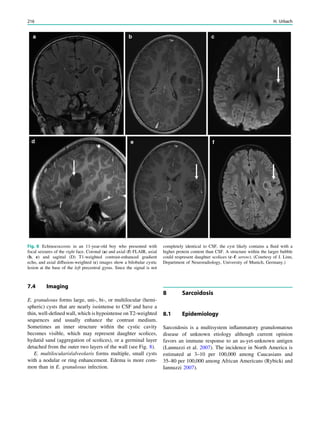

Fig. 1 An 8-year old girl presented with two focal motor seizures and

postictal left arm paralysis. MRI shows superior sagittal sinus

thrombosis (a–c, arrows) with two small hemorrhages at the gray

matter–white matter junction in the right frontal lobe (a, hollow

arrows)